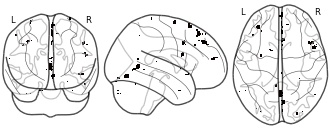

Neuroanatomical basis of concern-based altruism in virtual environment: DBM...

EmailClick to copy linkLink copied Cite(2018). Neuroanatomical basis of concern-based altruism in virtual environment: DBM positive correlation mask with EC [Dataset]. http://identifiers.org/neurovault.image:29233niftiAvailable download formatsUnique identifierhttps://identifiers.org/neurovault.image:29233Dataset updatedJun 30, 2018License

Costly altruism entails helping others at a cost to the self and prior work shows that empathic concern (EC) for the well-being of distressed and vulnerable individuals is one of the primary motivators of such behavior. However, extant work has investigated costly altruism with paradigms that did not feature self-relevant and severe costs for the altruist and have solely focused on neurofunctional, and not neuroanatomical, correlates. In the current study, we used a contextually-rich virtual reality environment to study costly altruism and found that individuals who risked their own lives in the virtual world to try to save someone in danger had enlarged right anterior insula and exhibited greater empathic concern than those who did not. These findings add to the growing literature showing the role of caring motivation in promoting altruism and prosociality and its neural correlates in the right anterior insula.

TwitterNeuroanatomical basis of concern-based altruism in virtual environment: DBM positive correlation mask with EC

Costly altruism entails helping others at a cost to the self and prior work shows that empathic concern (EC) for the well-being of distressed and vulnerable individuals is one of the primary motivators of such behavior. However, extant work has investigated costly altruism with paradigms that did not feature self-relevant and severe costs for the altruist and have solely focused on neurofunctional, and not neuroanatomical, correlates. In the current study, we used a contextually-rich virtual reality environment to study costly altruism and found that individuals who risked their own lives in the virtual world to try to save someone in danger had enlarged right anterior insula and exhibited greater empathic concern than those who did not. These findings add to the growing literature showing the role of caring motivation in promoting altruism and prosociality and its neural correlates in the right anterior insula.